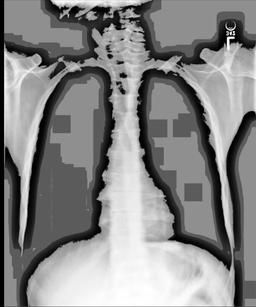

A.4 Data curation of imaging datasets

Large datasets often contain instances that are mislabelled or out of distribution [35]. We used BioViL-T to perform pairwise ranking of instances in MIMIC-CXR (Section 3.3, ) and selected representative examples found in the dataset. Our method is able to select the most appropriate image for a range of different image-acquisition or image-processing issues (Figure A.7).

We found that many lateral acquisitions in the dataset were unexpectedly labelled as frontal (Figure 7(a)). Some images contained only noise (Figure 7(b)), non-human samples (Figures 7(d) and 7(e)) or incorrect anatomy (Figure 7(g)). Often, acquisitions with an incomplete field of view (FOV) (i.e., the lungs are not completely visible) were repeated (Figure 7(c)). Lastly, post-processed images were detected by the algorithm such as contrast-enhanced scans (Figure 7(i)) that are not often used for diagnostic purposes in clinical practice.